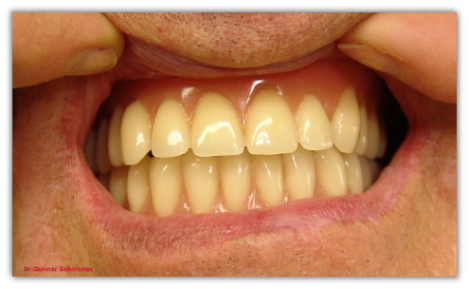

Beide Prothesen sin im Mund zu sehen.